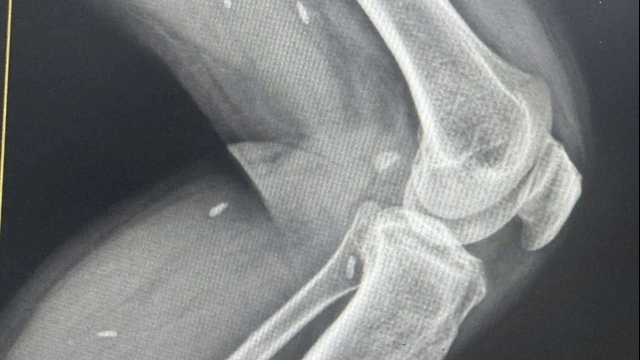

![]() |

| Hệ sinh thái y tế Tâm Anh đầu tư đồng bộ máy móc công nghệ cao hiện đại hàng đầu thế giới như “siêu máy” chụp CT hơn 100.000 lát cắt, Robot phẫu thuật Da Vinci Xi thế hệ mới… phục vụ khám chữa bệnh hiệu quả. |